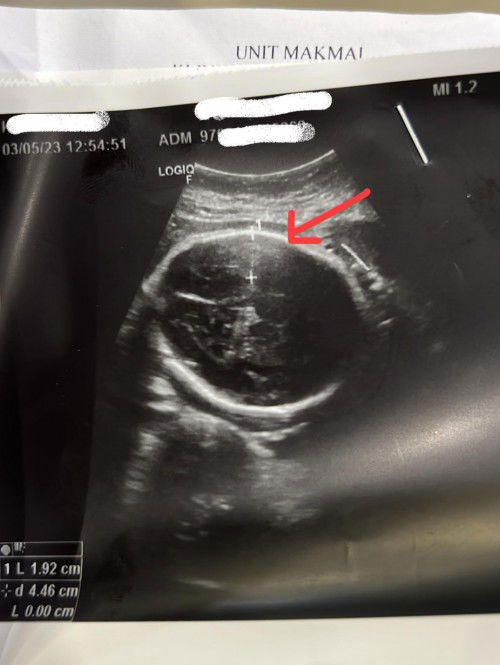

Scan Kepala Baby

Assalamualaikum mommies 😊 Nk mintak pandangan mommies yg mungkin ada pengalaman mcm sy. Harini scan baby 31w2d kat KK. Alhamdulillah baby membesar ikut minggu kandungan, kepala pn dh kat bawah. Air ketuban & uri pn okay semua. Cuma dekat kepala baby je doktor rasa suspicious takut2 ada bleeding atau apa2 yg abnormal. Then sy kene refer pakar O&G untk scan lebih details lagi 17/5 nanti. Perlu tak sy pegi scan swasta dulu? Atau mungkin normal je nie cuma tggu je appointment dgn pakar O&G tu nanti?